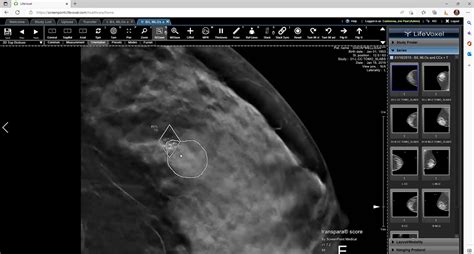

Hey there, guys! Let’s chat about something incredibly vital: breast cancer detection . It’s a topic that touches so many lives, and honestly, the thought of someone missing an early diagnosis is just heartbreaking. But what if I told you that cutting-edge technology, specifically deep learning and Artificial Intelligence (AI) , is rapidly changing the game? We’re talking about a genuine revolution in how we identify this disease, making detection potentially earlier, more accurate, and more accessible than ever before. For years, we’ve relied on traditional methods, which are good, but they come with their own set of challenges. Now, with the power of AI and its incredible ability to learn from vast amounts of data, we’re seeing breakthroughs that promise to transform healthcare and, crucially, save countless lives. This isn’t just about fancy algorithms; it’s about giving patients a better chance, easing the burden on medical professionals, and bringing hope to families worldwide. We’re on the cusp of a new era where technology isn’t just an aid but a fundamental partner in the fight against one of the most prevalent cancers. So, buckle up, because we’re diving deep into how deep learning breast cancer detection is becoming a reality, and why it’s such a big deal for all of us.

When it comes to breast cancer detection , the traditional approach has been the cornerstone of our efforts for decades. Mammography , for instance, has been the go-to method for screening, and it has undoubtedly saved many lives by catching tumors that might otherwise go unnoticed. However, despite its established role, it’s not without its limitations and challenges, and understanding these is key to appreciating why new technologies like deep learning are so desperately needed. Think about it, guys: traditional mammograms can be uncomfortable, and sometimes, they don’t give a clear picture, especially for women with dense breast tissue. This can lead to what we call false positives , where a woman is told there might be an issue, causing immense stress and anxiety, only for further tests to reveal it was nothing. On the flip side, we also face the challenge of false negatives , where a small, insidious tumor is missed, potentially delaying crucial treatment. These aren’t just statistics; these are real people, real fears, and real missed opportunities for early detection .

Beyond the technical aspects of the imaging itself, there’s also the human element. Radiologists , who are truly incredible medical professionals, spend countless hours poring over these images, looking for subtle signs of abnormality. It’s a highly skilled, incredibly demanding job that requires immense concentration and expertise. But let’s be honest, even the most experienced human eye can get tired, or miss something tiny in a vast sea of data. The sheer volume of mammograms to be reviewed is staggering, and the workload on radiologists is constantly increasing. This can lead to variability in interpretations, where two different radiologists might come to slightly different conclusions, or a radiologist might miss a nuanced detail that, in retrospect, was indicative of cancer. This isn’t a criticism of our amazing healthcare providers; it’s just the reality of relying solely on human interpretation for such a critical task. The goal isn’t to replace these experts but to equip them with advanced tools that can act as a powerful second pair of eyes, enhancing their capabilities and ensuring greater consistency and accuracy in breast cancer detection . This is precisely where the promise of deep learning shines through, offering a revolutionary way to support and augment current screening practices, aiming to reduce both false positives and false negatives, and ultimately, improve patient outcomes. The challenges of the traditional path highlight the urgent need for innovative solutions, and AI is stepping up to the plate in a big way.